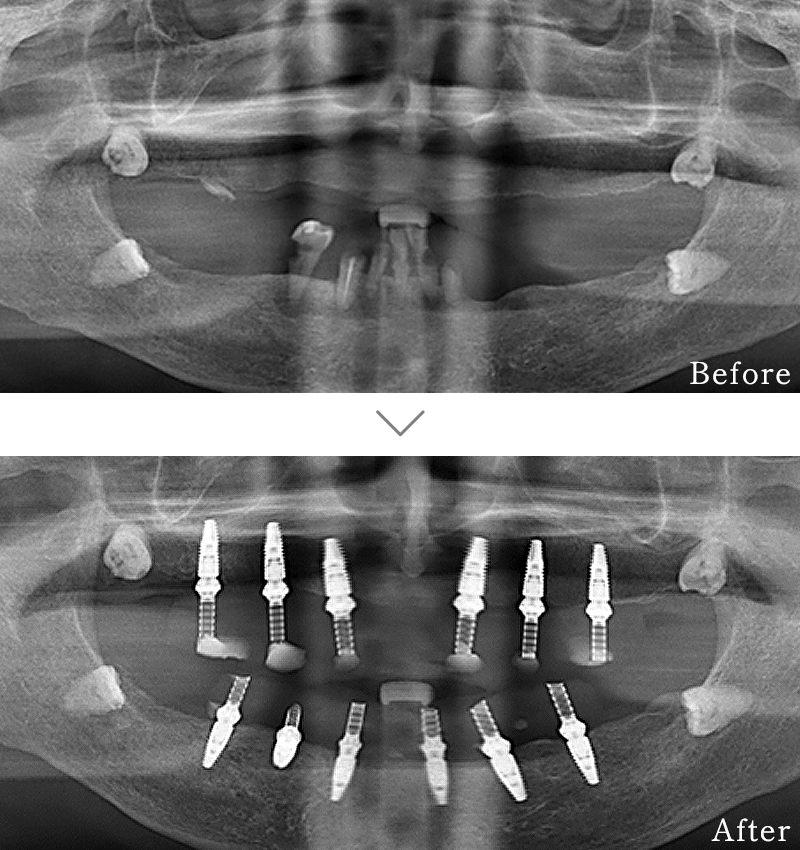

CASE3

主訴 入れ歯も合わず、しっかりと噛んで食事ができないとのことで来院されました。

治療法 上下ともにALL-ON-6と呼ばれる最少本数のインプラントで全ての歯を回復する治療を行なっています。歯の部分は全てセラミックで作成されています。

治療期間 10ヶ月

※矯正治療の期間は含まれておりません。

費用 CT:16,500円(税込)

+ インプラント治療:1,051,600円(税込)

+ 造骨処置(GBR):176,000円(税込)

合計:1,244,100円(税込)

※矯正治療費は含まれておりません。

副作用

• 歯周病に感染・発症し重度に進行するとインプラントが抜けてしまうことがあります。

• 手術後は数日間腫れが出る場合があります。

• 歯肉移植時は、採取部位からの出血が数日続くことがあります。